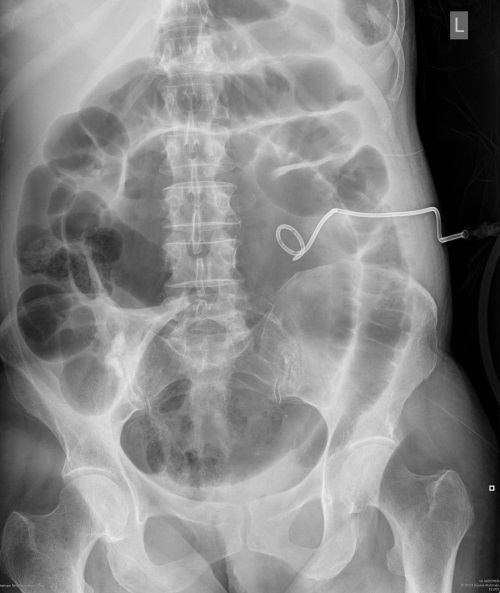

What does this AXR show?

Small bowel obstruction is clearly visible on this film (note the valvulae conniventes, mucosal folds, that cross the full width of the bowel) secondary to caecal volvulus. Note the left nephrostomy tube in-situ.